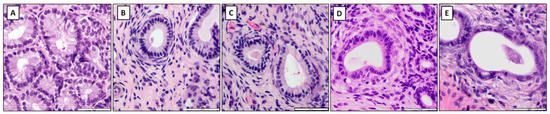

Background and Objectives: Damage to the vocal folds frequently results in fibrosis, which can degrade vocal quality due to the buildup of collagen and modifications in the extracellular matrix (ECM). Conventional treatments have shown limited success in reversing fibrotic changes. Hepatocyte growth factor (HGF) and c-Met-targeting antibodies are promising due to their potential to inhibit fibrosis and promote regeneration. This research examines the effectiveness of injections containing c-Met agonistic antibodies relative to HGF in reducing fibrosis within a rat model of vocal fold injury. Materials and Methods: Forty-five Sprague Dawley rats were divided into three groups, which were HGF, c-Met agonistic antibody, and the control (PBS). The right vocal folds were injured and treated with HGF or c-Met agonistic antibody injections. RNA isolation and quantitative real-time PCR were performed to assess mRNA levels of fibrosis-related markers at 1 and 2 weeks post-injury. Histopathological analysis was conducted at 3 weeks to evaluate collagen and hyaluronic acid (HA) deposition. Results: Both the HGF and c-Met groups demonstrated reduced type III collagen mRNA expression compared to the PBS group. The c-Met group uniquely maintained fibronectin levels closer to normal. Additionally, the c-Met group showed significantly upregulated expression of hyaluronan synthase (HAS) 1 and HAS 3 at 2 weeks post-injury, indicating enhanced HA synthesis. Histological analysis showed significantly lower collagen deposition and higher HA in the c-Met group than in PBS, confirming superior anti-fibrotic effects and ECM restoration. Conclusions: c-Met agonistic antibody injections outperformed HGF in reducing fibrosis, upregulating HAS expression, and promoting HA deposition in injured vocal folds, highlighting its potential as a superior therapeutic approach for preventing fibrosis and enhancing ECM quality in vocal fold injuries. Further research on functional outcomes in larger models is recommended to validate these findings. Full article